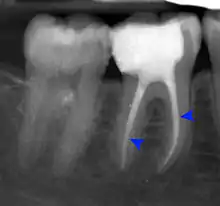

- Radiographs utilized to find dental caries and bone loss laterally or at the apex.

The periodontal ligament becomes inflamed and there may be pain when biting or tapping on the tooth. On an X-ray, bone resorption appears as a radiolucent area around the end of the root, although this does not manifest immediately.[10]: 228 Acute apical periodontitis is characterized by well-localized, spontaneous, persistent, moderate to severe pain.[6]: 125–135 The alveolar process may be tender to palpation over the roots. The tooth may be raised in the socket and feel more prominent than the adjacent teeth.[6]: 125–135